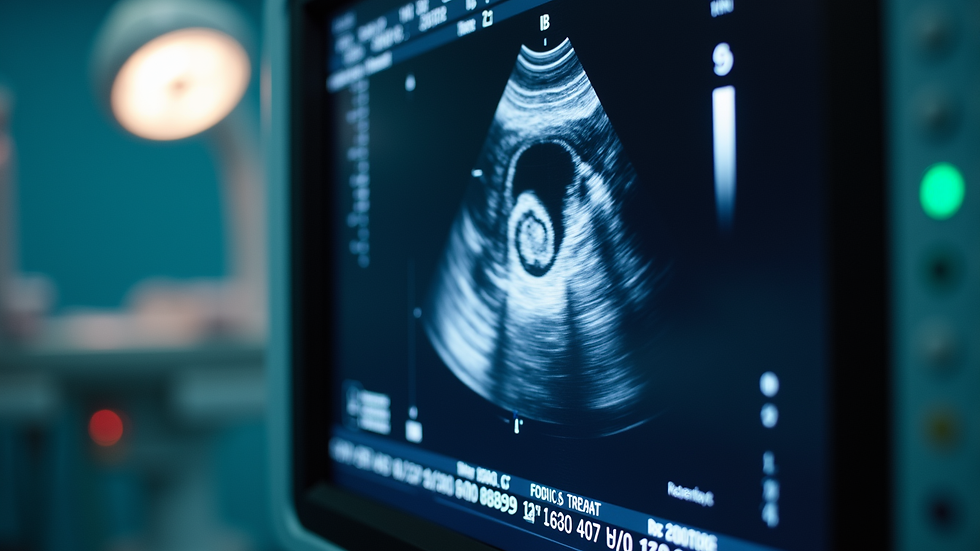

Liver imaging diagnostics refer to a range of non-invasive tests that create detailed images of your liver. These tests help detect abnormalities such as tumors, cysts, fatty liver disease, cirrhosis, and other liver conditions. The most common imaging methods include ultrasound, CT scans, and MRI.

Ultrasound is often the first step because it is safe, painless, and widely available. It uses sound waves to produce images of the liver and surrounding organs. CT scans and MRIs provide more detailed images and are used when further investigation is needed.

Ultrasound imaging is a common and effective method for liver diagnostics.